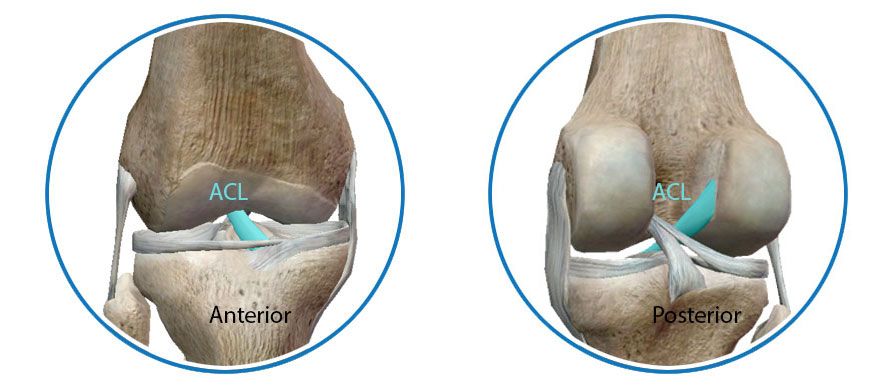

Οι 2 χιαστοί σύνδεσμοι (Πρόσθιος ΠΧΣ και Οπίσθιος ΟΧΣ) λειτουργούν ως σύστημα, το οποίο αποτρέπει την προσθιοπίσθια και τη στροφική αστάθεια κατά την κίνηση της άρθρωσης.

Ο πρόσθιος χιαστός σύνδεσμος (ΠΧΣ) αποτελεί έναν πολύ σημαντικό για την σταθερότητα του γόνατος σύνδεσμο. Αποτρέπει την πρόσθια ολίσθηση και στροφή της κνήμης σε σχέση με τον μηρό. Ο τραυματισμός του ΠΧΣ γίνεται με μηχανισμό απότομης επιβράδυνσης σε αλλαγή κατεύθυνσης.

Ο ΟΧΣ βρίσκεται στο οπίσθιο τμήμα της άρθρωσης του γόνατος, συνδέει το μηριαίο με την κνήμη και παρεμποδίζει την υπερβολική οπίσθια μετατόπιση της κνήμης.

Ο ΠΧΣ και ο ΟΧΣ συνδέουν τα οστά μεταξύ τους.Ονομάζονται χιαστοί γιατί οι δέσμες των ινών τους χιάζονται στην πορεία που διαγράφουν μέσα στην άρθρωση.